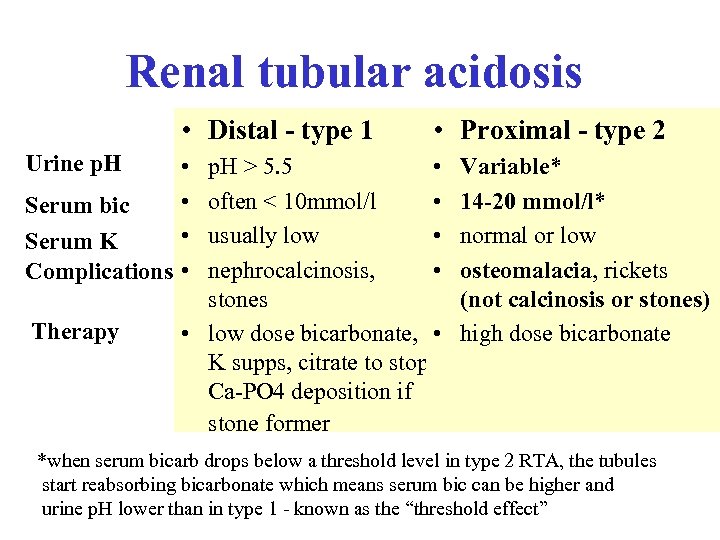

Renal tubular acidosis • Distal - type 1 Urine p. H • • Serum bic • Serum K Complications • Therapy p. H > 5. 5 often < 10 mmol/l usually low nephrocalcinosis, stones • low dose bicarbonate, K supps, citrate to stop Ca-PO 4 deposition if stone former

Renal tubular acidosis • Distal - type 1 Urine p. H • • Serum bic • Serum K Complications • Therapy p. H > 5. 5 often < 10 mmol/l usually low nephrocalcinosis, stones • low dose bicarbonate, K supps, citrate to stop Ca-PO 4 deposition if stone former

Renal tubular acidosis • Distal - type 1 Urine p. H • • Serum bic • Serum K Complications • Therapy • Proximal - type 2 p. H > 5. 5 • often < 10 mmol/l • usually low • nephrocalcinosis, • stones • low dose bicarbonate, • K supps, citrate to stop Ca-PO 4 deposition if stone former Variable* 14 -20 mmol/l* normal or low osteomalacia, rickets (not calcinosis or stones) high dose bicarbonate *when serum bicarb drops below a threshold level in type 2 RTA, the tubules start reabsorbing bicarbonate which means serum bic can be higher and urine p. H lower than in type 1 - known as the “threshold effect”